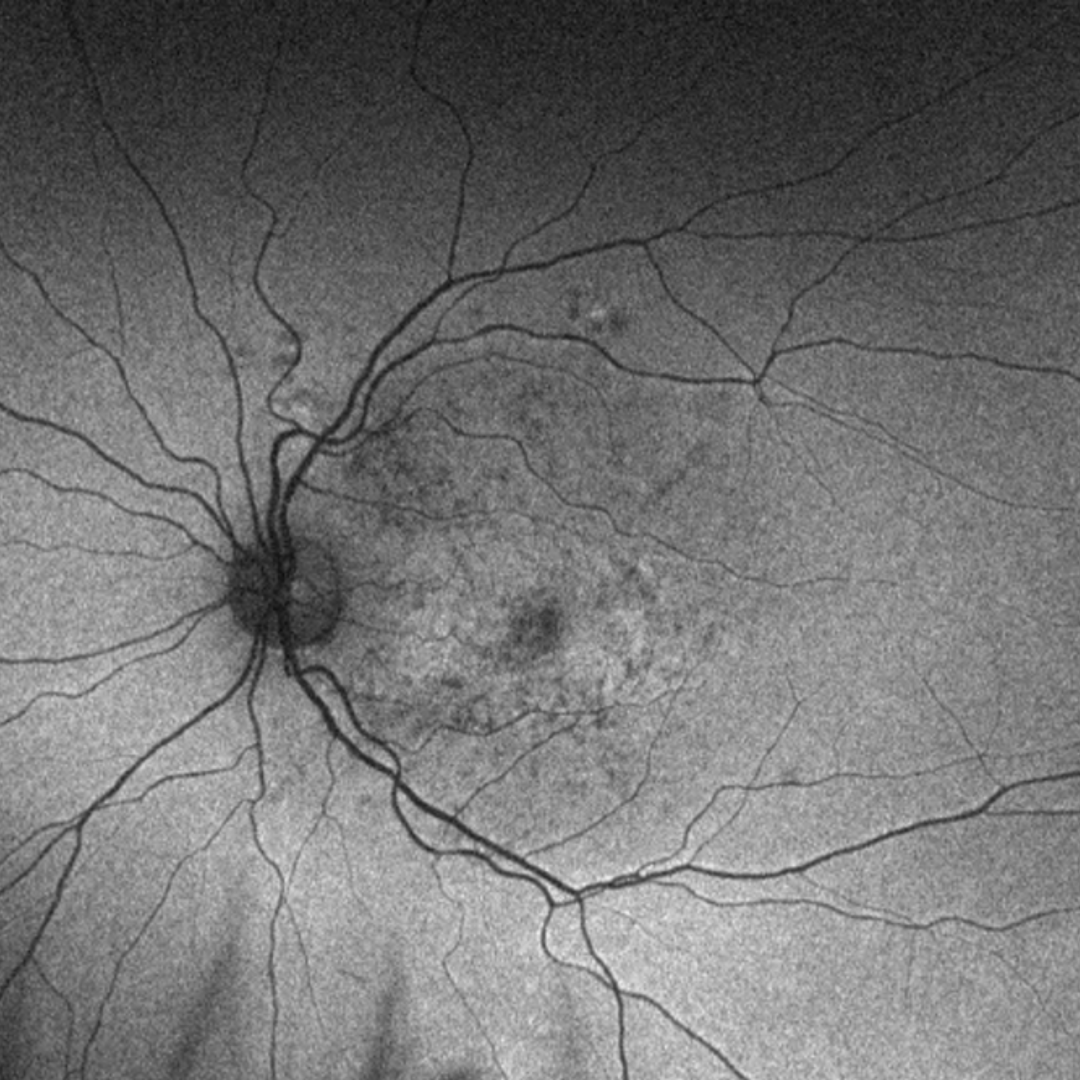

Fundus pulverulentus is the rarest type of pattern dystrophy and is characterised by coarse pigment mottling at the macula. It usually has minimal effect on vision however, choroidal neovascularisation can occur in rare cases.

Case 1

A 48-year-old Caucasian female with best-corrected visual acuity of 6/6 (20/20) in each eye.